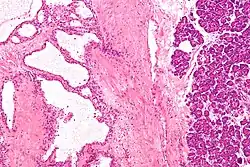

![]() صورة مجهرية تظهر ورم غدي كيسي مصلي في البنكرياس. صبغة الهيماتوكسيلين واليوزين. صورة مجهرية تظهر ورم غدي كيسي مصلي في البنكرياس. صبغة الهيماتوكسيلين واليوزين. | |

ورم غدي كيسي مصلي برأس البنكرياس.

صورة مجهرية ورم غدي كيسي مصلي (تكبير عال جدًا).jpg.webp)